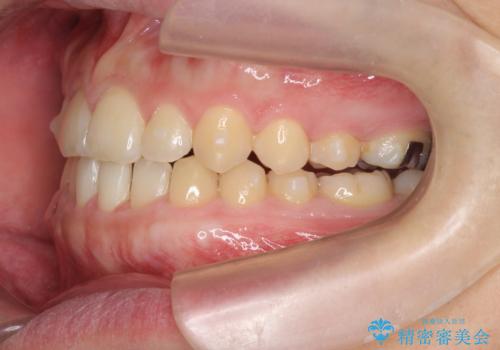

- 前歯の噛み合わせが反対になっていること、前歯の見た目の改善を希望され来院されました。

詳細な矯正検査の結果、顎の歪みが見られたため大きく歯を動かす治療ではなく前歯を主に並べることで前歯の前後関係を改善していきます。

前歯を主に動かす部分矯正であることからマウスピース矯正インビザラインによる治療を計画します。